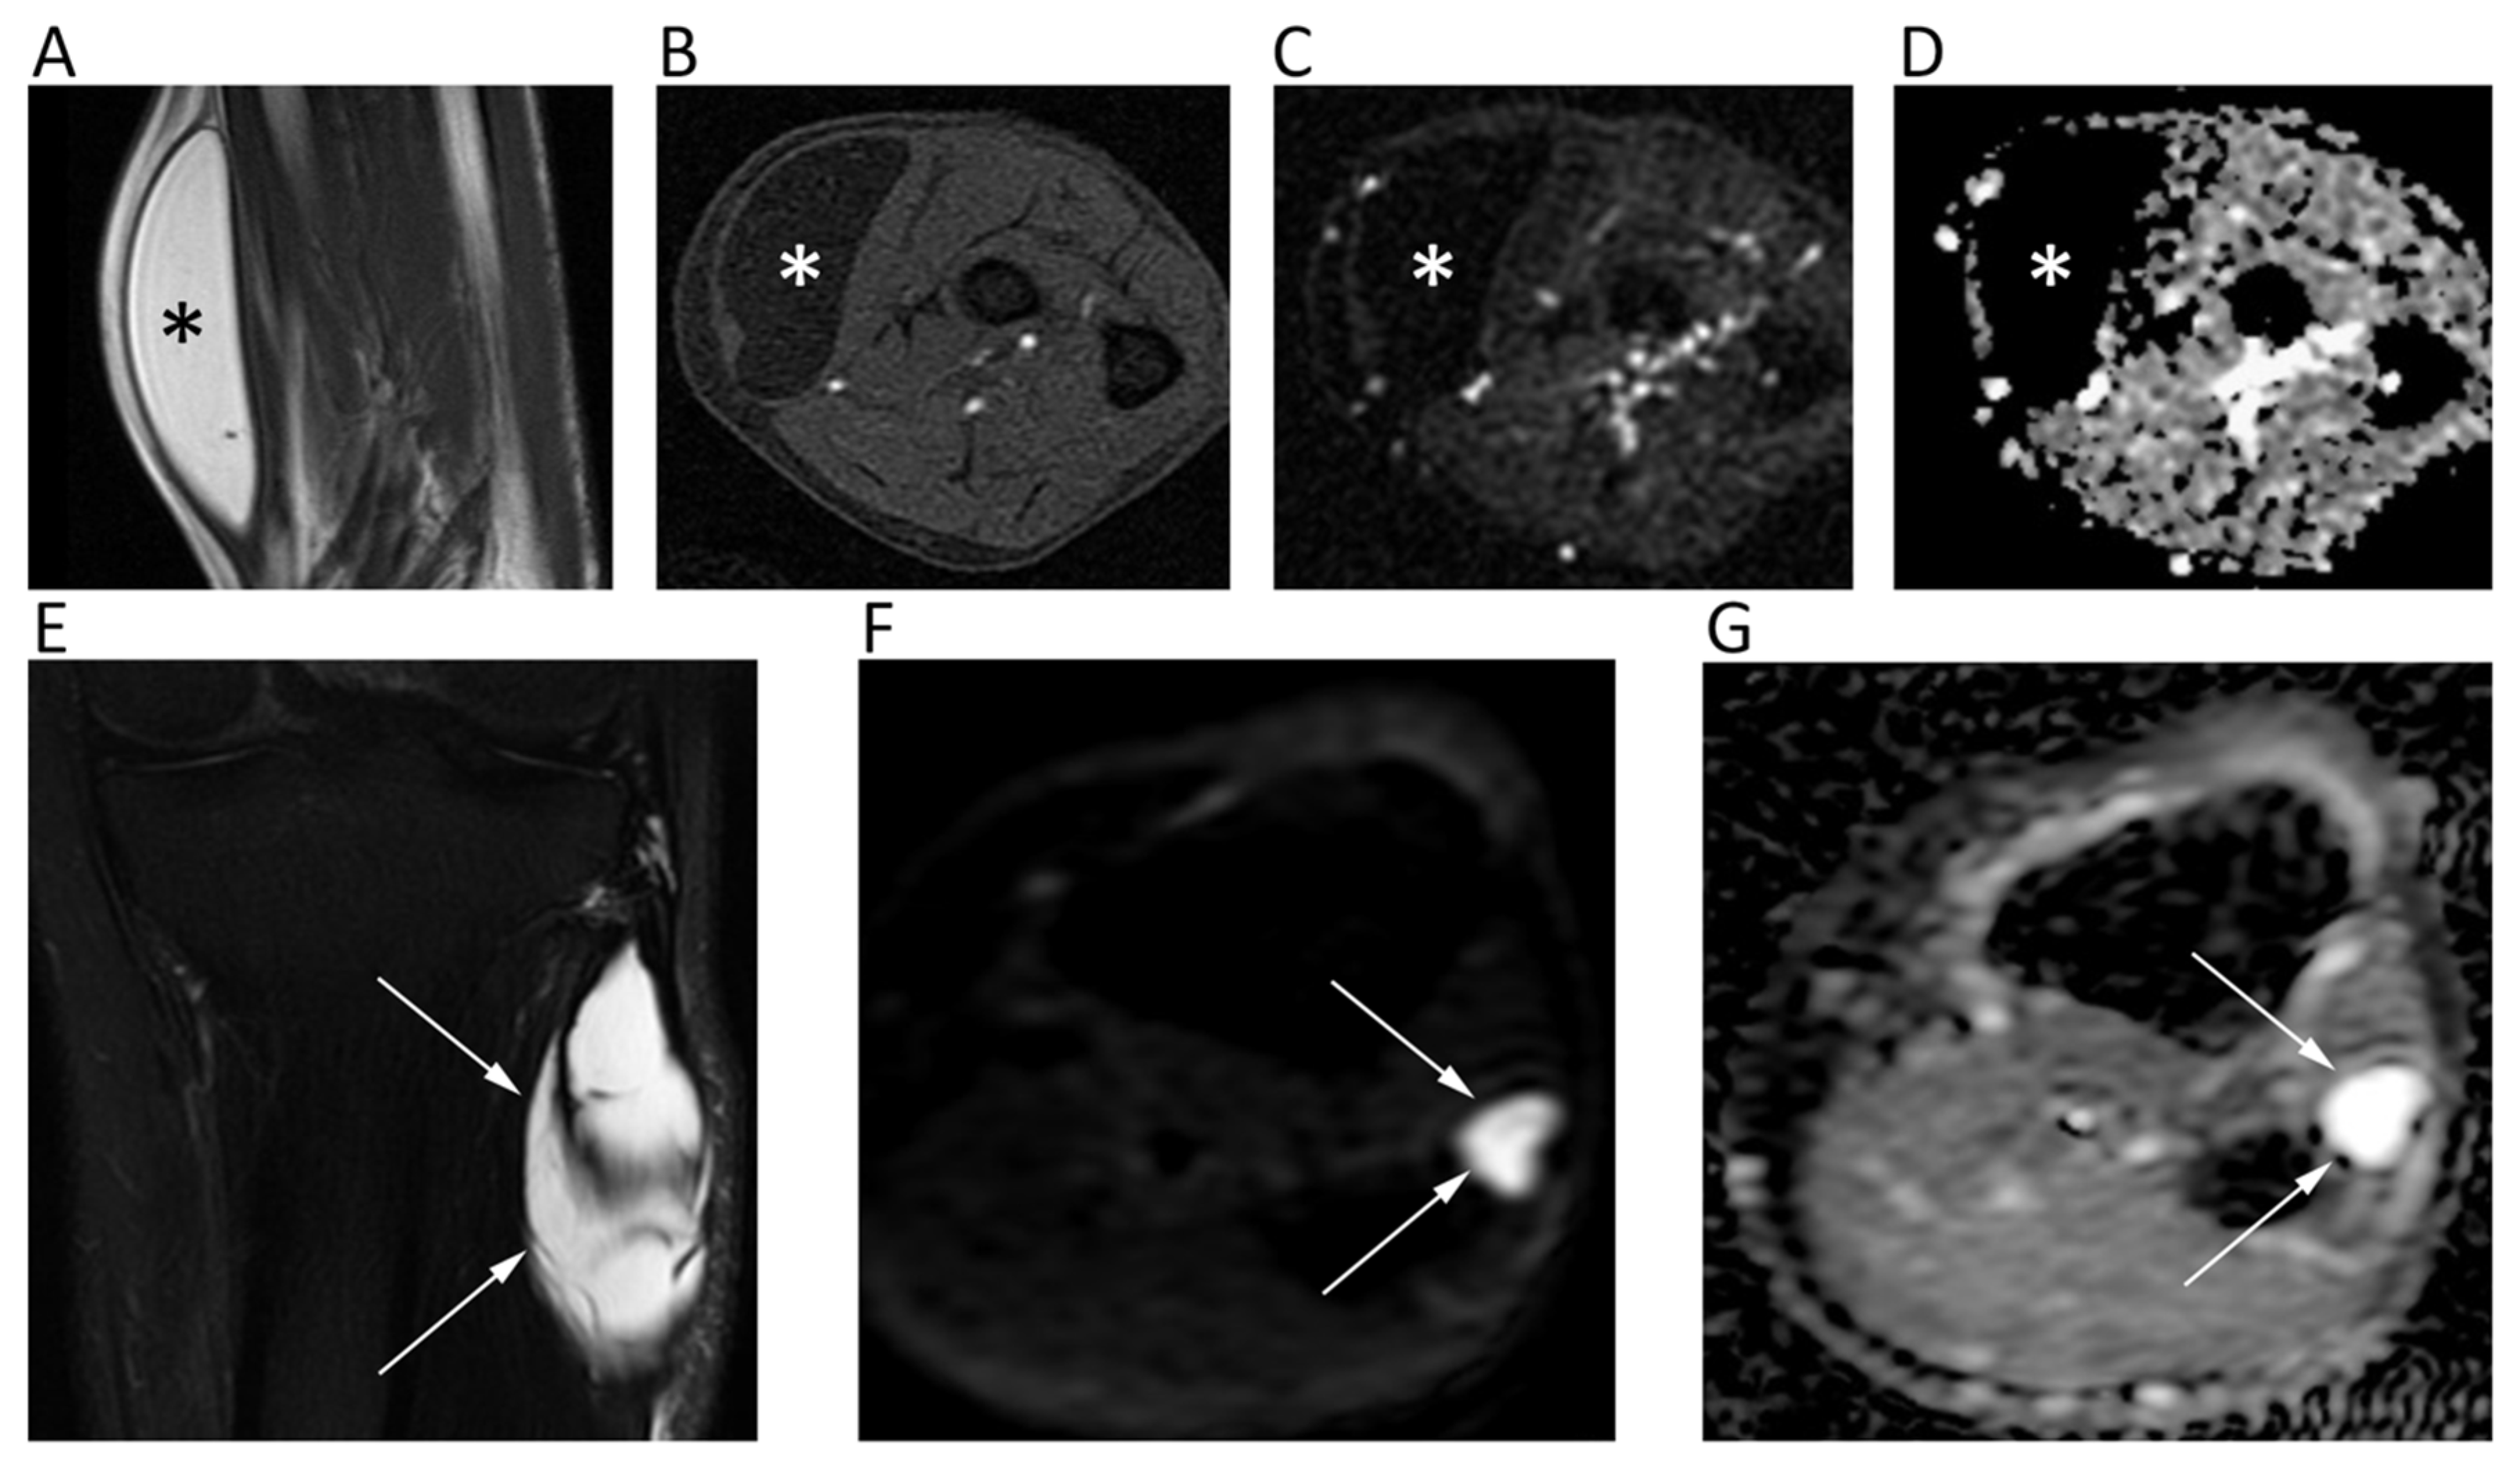

As a general rule, malignant BTs show lower ADC compared to benign BTs [93]. However, it has been reported that certain types of benign BT may present low ADC (<1.0 × 10−3 mm2/s), such in the case of non-ossifying fibroma or giant cell tumor, probably due the condensed collage fibers of the former and the elevated cellularity of the latter [95]. Thus, DWI should not be used alone, but as a supplementary tool together with conventional MRI sequences. ADC is generally low in osteosarcoma, despite certain variability related to the different histological characteristics, with the solid cellular tumor component showing lower ADC compared to necrotic parts [96]. The use of ADC in chondrosarcomas is controversial, with DWI having a limited role in differentiating between benign and malignant cartilage tumors, due to the fact that tumor cells are more exiguous within the myxoid matrix [93]. Indeed, Douis et al. showed that ADC did not significantly differ between low-grade and high-grade chondrosarcomas (Figure 12A–E) [97].

Figure 12.

The left femur G3 chondrosarcoma (A–E) of a 76-year-old male patient. Axial T2w image (A) shows a hyperintense bone lesion with a large posterior soft tissue mass presenting poor contrast enhancement on fat-suppressed T1w image (B). The lesion shows high signal on b = 0 DWI image (C), decreased signal on b = 1000 DWI image (D), and unrestricted pattern of diffusion on the corresponding ADC map (E, mean ADC: 2.303 × 10−3 mm2/s). The Ewing sarcoma (F–J) of the left iliac bone of a 31-year-old male patient. The tumor presents as an esofitic bone lesion with intermediate signal on axial T2w image (F) and high signal on axial STIR image (G). The lesion shows intermediate-high signal on b = 0 DWI image (H), higher signal on b = 1000 DWI image (I), and restricted pattern of diffusion on the corresponding ADC map (J, mean ADC: 0.899 × 10−3 mm2/s).

With regard to spine, it has been shown that metastasis and malignant spinal BT generally show lower ADC compared to benign lesions [98]. When considering only primary spinal BTs, it has to be taken into account that certain overlap may exist for ADC values, although primary hypercellular malignant spinal BTs (such as Ewing’s sarcoma, lymphomas, or multiple myelomas) usually show very low ADC (<1.0 × 10−3 mm2/s) (Figure 12F–J) [93,98]. When differentiating benign from malignant vertebral fractures, it has to be considered that literature usually refers to benign fractures as those that arise from osteoporosis and not from benign tumors. In such cases, benign fractures usually show higher ADCs [99]. A recent meta-analysis by Luo et al. confirmed the utility of ADC, suggesting one to use a threshold of mean ADC < 1.4 × 10−3 mm2/s to reasonably detect malignancy [99].